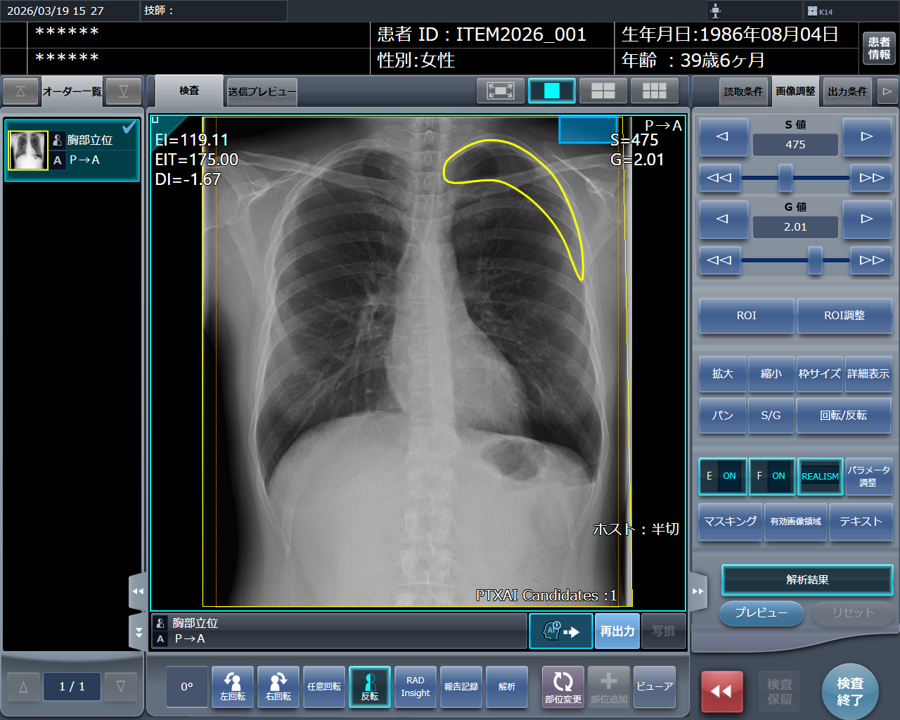

「STAT Link」は、気胸検出機能、所見報告・記録機能、「RADInsight(ラドインサイト)」との連携機能により、STAT画像所見報告のワークフローを包括的に支援します。

■気胸検出機能(「CXR Finding-i 気胸検出タイプ」との連携)

気胸の診断支援を行うプログラム「CXR Finding-i 気胸検出タイプ」と連携することで、ガイドラインにおいて一般撮影で診療放射線技師が発見した場合に報告すべきSTAT画像所見の一つに挙げられている気胸の候補を高精度で検出することができます。

コンピューターのスクリーンショット

「CXR Finding-i 気胸検出タイプ」により解析された気胸の検出領域を表示